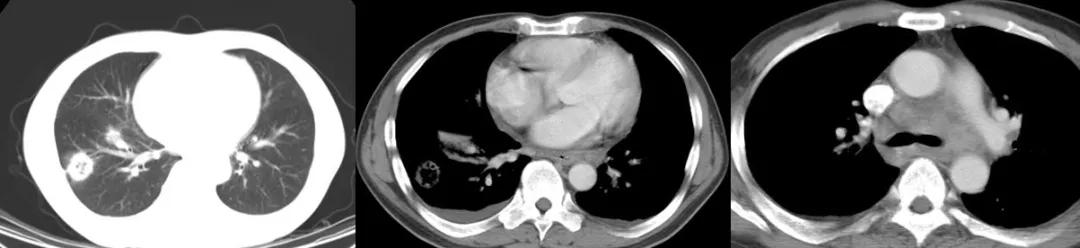

病例5:

男,52岁,溶血性贫血,激素治疗43天。

最初完全按照大叶型肺炎、细菌性肺炎治疗,没有明显效果。最后出现播散,用了机械通气,出现气胸等等。

病例6:

这位患者是急性单核细胞性白血病,化疗2个疗程后出现病症——发热、咳嗽,咳黄痰,很多人会因此想到细菌性肺炎。但事实上,做了气管镜、采样、活检,证实有大量的抗酸杆菌。肺组织活检证实是肉芽肿改变,最后确诊肺结核。

经过治疗以后明显吸收好转:

病例7:

患者是混合性结缔组织疾病,激素治疗6个月后出现发热,肺部病灶明显增多,两侧情况不一样,我们冒了很大风险给他做支气管肺泡灌洗,做刷检、做活检,刷检时也找到了抗酸杆菌,但活检的结果是:既有一般的结缔组织的肉芽肿性改变,同时也看到有结核的干酪样坏死。因为患者是在激素减量过程中出现的症状,所以我们考虑是既有结缔组织疾病,又合并了肺结核。